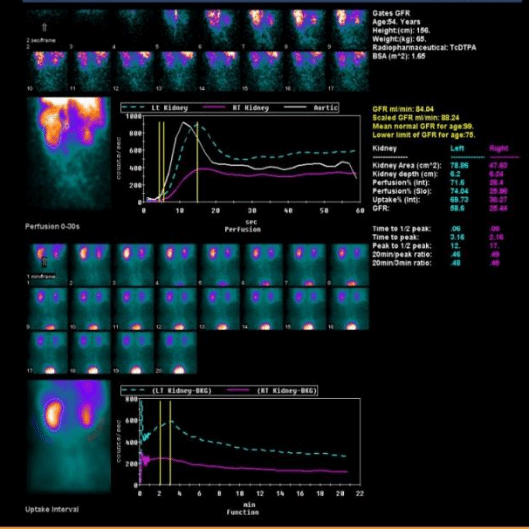

1、肾肿瘤患者评估分肾功能

左图,女,60岁,右肾下极占位,肾功能正常。

右图,女,54岁,右肾占位,导致右肾功能受损(右侧GFR 25)。

以上三组病例告诉我们,相同的疾病,对肾脏的影响可能不同,肾动态显像可以帮助我们定量的判断两个肾脏分别的功能。